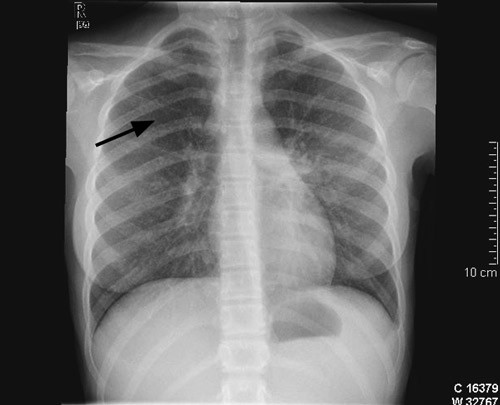

Ved innkomst var det normal respirasjon og normale auskultasjonsfunn over lungene. Det var ingen lymfeknutesvulst. Ho var palpasjonsøm i nedre høgre kvadrant av abdomen. Temperaturen var 38,3 °C. CRP var 49 mg/l og senkingsreaksjonen 25 mm/t (< 10 mm/t). Dei andre blodprøvane var normale. Kalprotektin i avføring var 30 mg/kg (0 – 50 mg/kg). Røntgen av thorax viste sparsomme retikulonodulære fortettingar i båe lunger (fig 1). Spirometri viste nedsett lungefunksjon med restriktivt preg og nedsett diffusjonskapasitet (tab 1). Det vart så gjort høgoppløysings-CT av thorax som viste multiple små noduli med tilfeldig distribusjon i båe lunger, konsolidering i venstre underlapp og forstørra lymfeknutar i mediastinum og hilus (fig 2). MR av abdomen utan kontrast viste normale forhold.

Spørsmålet om eksponering for tuberkulose var gjentatte gongar tatt opp med pasient og pårørande, men med negativt resultat. Det vart hevda at alle nære pårørande var friske, og ingen av dei eldre i slekta hadde hatt tuberkulose tidlegare. Jenta hadde ikkje vore i høgendemiske område for tuberkulose eller i nærkontakt med innvandrarmiljø. Positiv Mantoux-test kan også skuldast infeksjon med atypiske mykobakteriar eller tidlegare BCG-vaksine (1). Pårørande meinte at jenta ikkje var vaksinert. Ein tydeleg positiv tuberkulinreaksjon hos ei jente med slike symptom og lungefunn talte likevel for tuberkulose sjølv om vi på dette tidspunktet ikkje hadde funne noka smittekjelde. Miliær tuberkulose er ein disseminert tuberkuløs infeksjon som har fått namn etter det typiske røntgenbiletet med små, utbreidde fortettingar som ser ut som hirsefrø (millet seed).